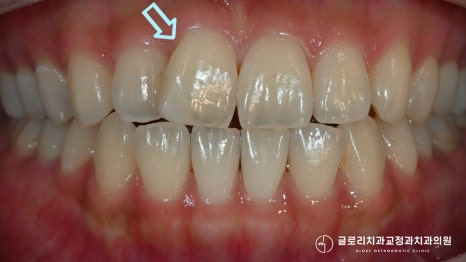

초진 사진을 보면 우측 상악 앞니 한 곳이

옆으로 틀어져 있는 듯한 모습이 관찰되었는데요.

이외에는 눈에 띄는 문제를 찾을 수 없을 정도로

정중선도 잘 맞고 있었으며

교합도 정상 범주에 속해 올바르게 맞물리고 있었죠.

수직 피개량이 약간 아쉽긴 했지만

다행히 음식을 끊거나 생활을 할 때

불편함이 없다는 말씀을 해주셨습니다.

어금니 교합도 1치대 2치대로 잘 맞고 있네요.